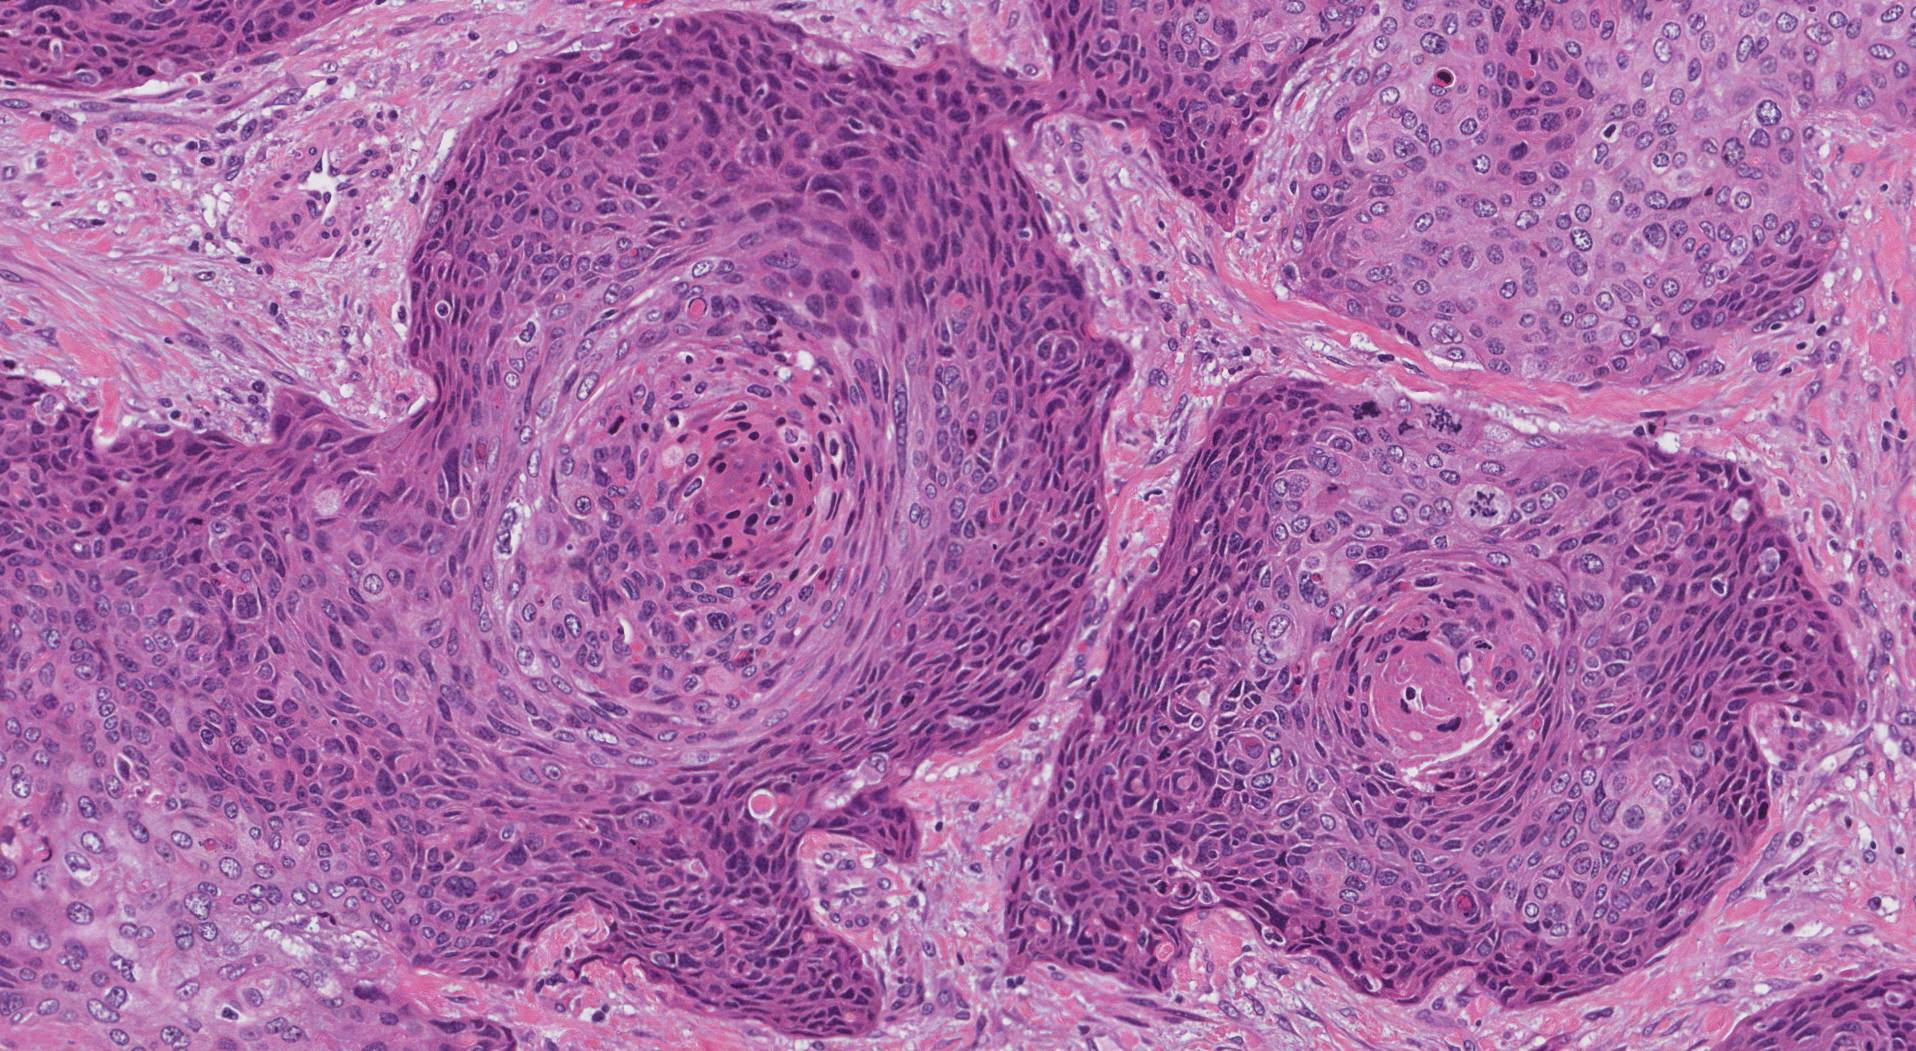

Плоскоклеточный Рак Кожи Картинки